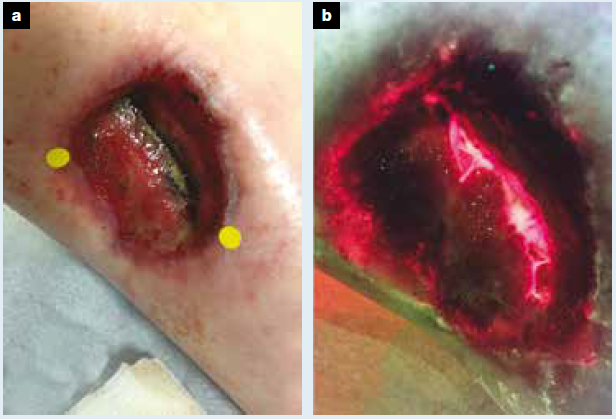

Diagnosis and treatment of the invasive extension of bacteria (cellulitis) from chronic wounds utilizing point-of-care fluorescence imaging

Andersen, A. et al. Int Wound J 2021